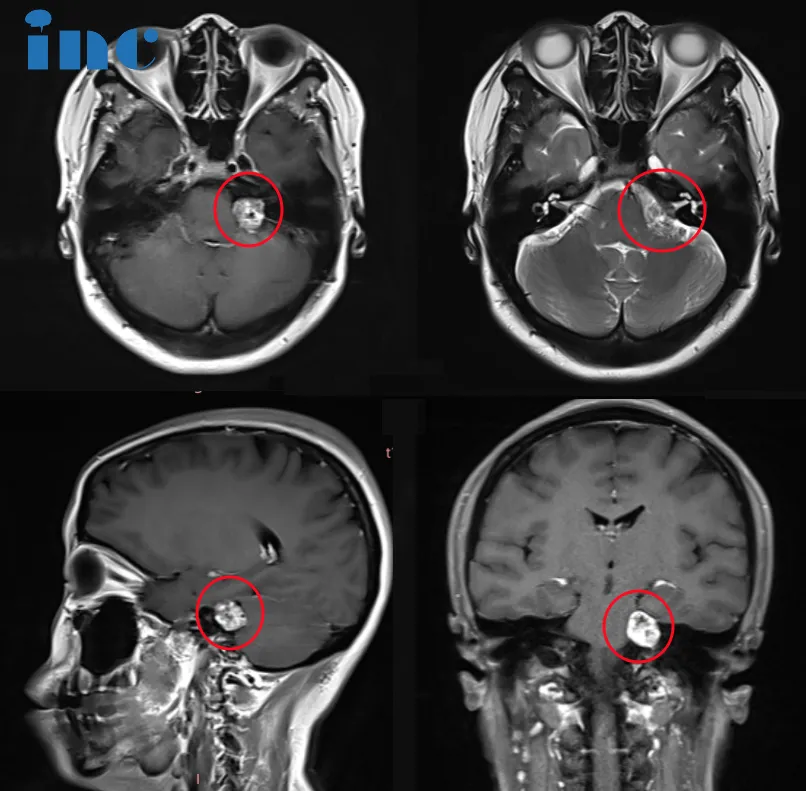

听神经瘤作为桥小脑角区最为常见的肿瘤,临床表现多样,比如听力下降、耳鸣、头痛、平衡失调,面部疼痛和麻木,这类肿瘤多见于30岁至60岁人群,很少见于年轻患者。 本期要分享的病例是...